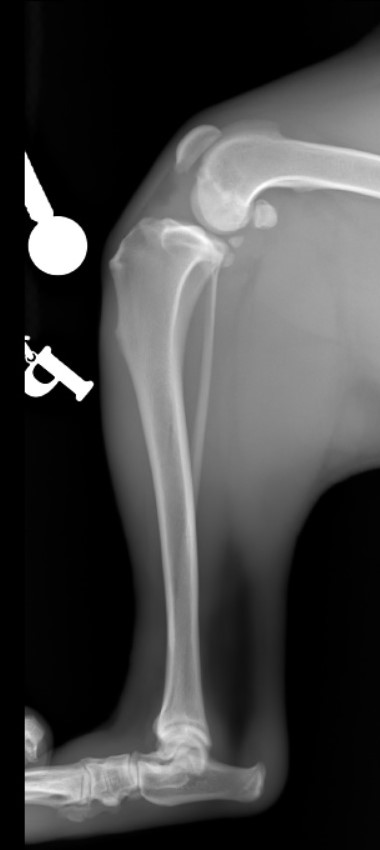

Nazywam się JJ :) Nigdy nie sądziłem, że będę potrzebował Waszej pomocy. Mam dopiero rok, urodziłem się 14 kwietnia 2019 roku. Lubię biegać, popiardywać, walczyć z odkurzaczem i dawać buziaczki człowiekom. Moi kochani opiekunowie przygarnęli takiego klopsa jakim jestem (a raczej byłem) ja... Mając zaledwie 4 miesiące zachorowałem na parwowirozę. Moje człowieki zrobili i oddali wszystko co mogli dać, abym wyzdrowiał. I tak się stało! Jednak zacząłem chorować bardzo szybko i po cichutku. Zaczęły boleć mnie moje tylnie nogi. Starałem się biegać, ale moje kolanka za bardzo bolały, więc ograniczyłem używania tylnich nóg do minimum podczas biegania. Żeby wejść na kanapę muszę bardzo się wysilić lub prosić moich człowieków, aby mi pomogli. Nie jestem w stanie wejść ani zejść po schodach bez odpoczynku. Moi kochani bracia i siostry (bo jesteśmy liczną rodzinką) patrzą na mnie z przykrością... Moje nietypowe siadanie na boku zaciekawiło domowników. Musiałem stworzyłem sobie garb, aby odciążyć nogi. Później pojawiły mi się guzki na prawej i lewej nodze. Na lewej nóżce guzek był troszkę większy, więc od razu pojechaliśmy do weterynarza. Niedobrze, bo guzki były już troszkę duże... Zapalenie, a może początek raka. Moja nowa Pani weterynarz zaczęła podejrzewać dysplazję biodrową. To mogłoby wyjaśnić moje “dziwaczne” siedzenie. Jednak nie była pewna, więc wysłała nas do specjalistów. Tam zrobili mi zdjęcia rentgenowskie i trochę mnie powyciągali. Bardzo mnie to bolało. Czułem wszystko, pomimo Jasia, którego dostałem. WERDYKT: Ześlizg główek w kościach kolana lewego i prawego o 33%, a to podobno bardzo dużo. Moje guzki to skutek rozlanego płynu zapalnego w kolanach. Moje lewe kolano choruje bardziej niż prawe. Jak się okazało nie urodziłem się z tym, ani nie jest to genetyczne. Po prostu zachorowałem na to. Moje kochane człowieki dostały dwie opcje.

Jedna to: operacja w kosztach 3 850,00 zł za jedną nogę (i to jak najszybciej...), a druga opcja to: amputacja kończyn.